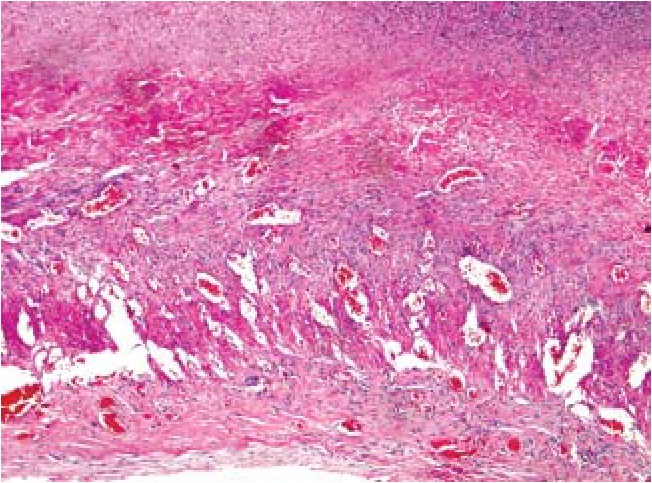

Наиболее характерным для острых перфоративных язв тонкой кишки было первичное повреждение слизистого слоя с развитием множественных некрозов эпителия (рис. 4, 8) на фоне массивной нейтрофильной инфильтрации (рис. 4–8) и значимых гемоциркуляторных расстройств в виде резкого полнокровия и тромбозов сосудов, а также геморрагического пропитывания как слизистого, так и подслизистого слоев (рис. 5, 7, 8), массивного разрастания в подслизистой основе грануляционной ткани (рис. 6) с исходом в фиброз и липоматоз (рис. 8).

Рис. 5. Интактная слизистая оболочка на фоне текущего перитонита: полнокровные сосуды, множественные очаговые кровоизлияния и геморрагическое пропитывание подслизистого и серозного слоя. Нейтрофильная инфильтрация подслизистого и серозного слоев. Окраска гематоксилин – эозином, ув. ×40